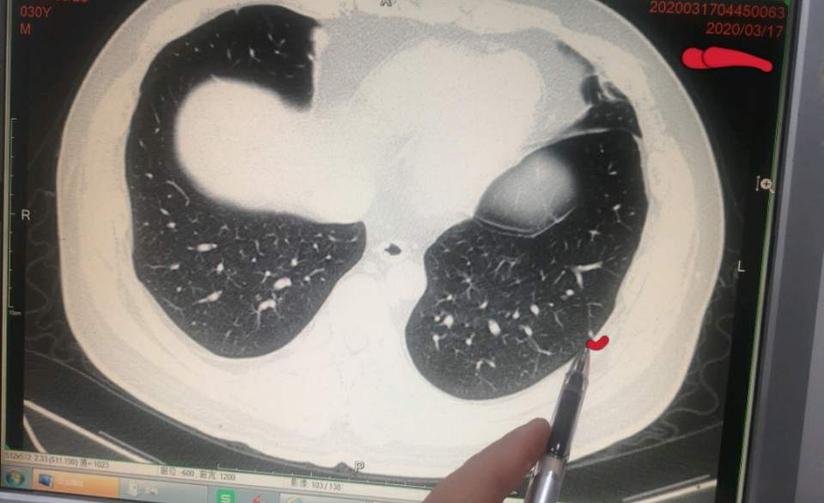

右肺纤维化病灶图片

红色箭头所示即为"纤维灶"